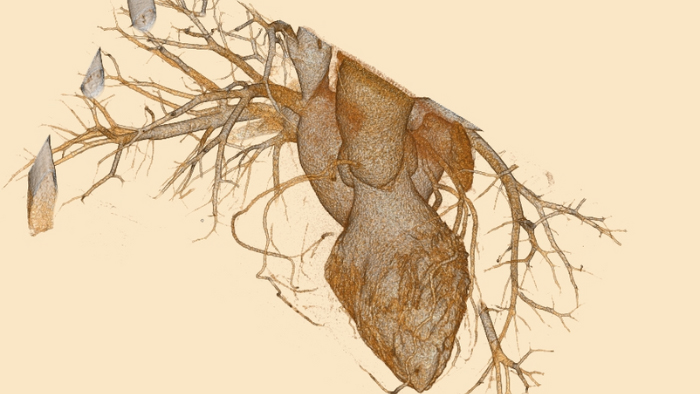

Deep clinical insights

Answer challenging diagnostic questions and significantly impact patient outcomes through the power of spectral-detector CT, which means that every scan for every patient gives you spectral results, allowing you to see more.